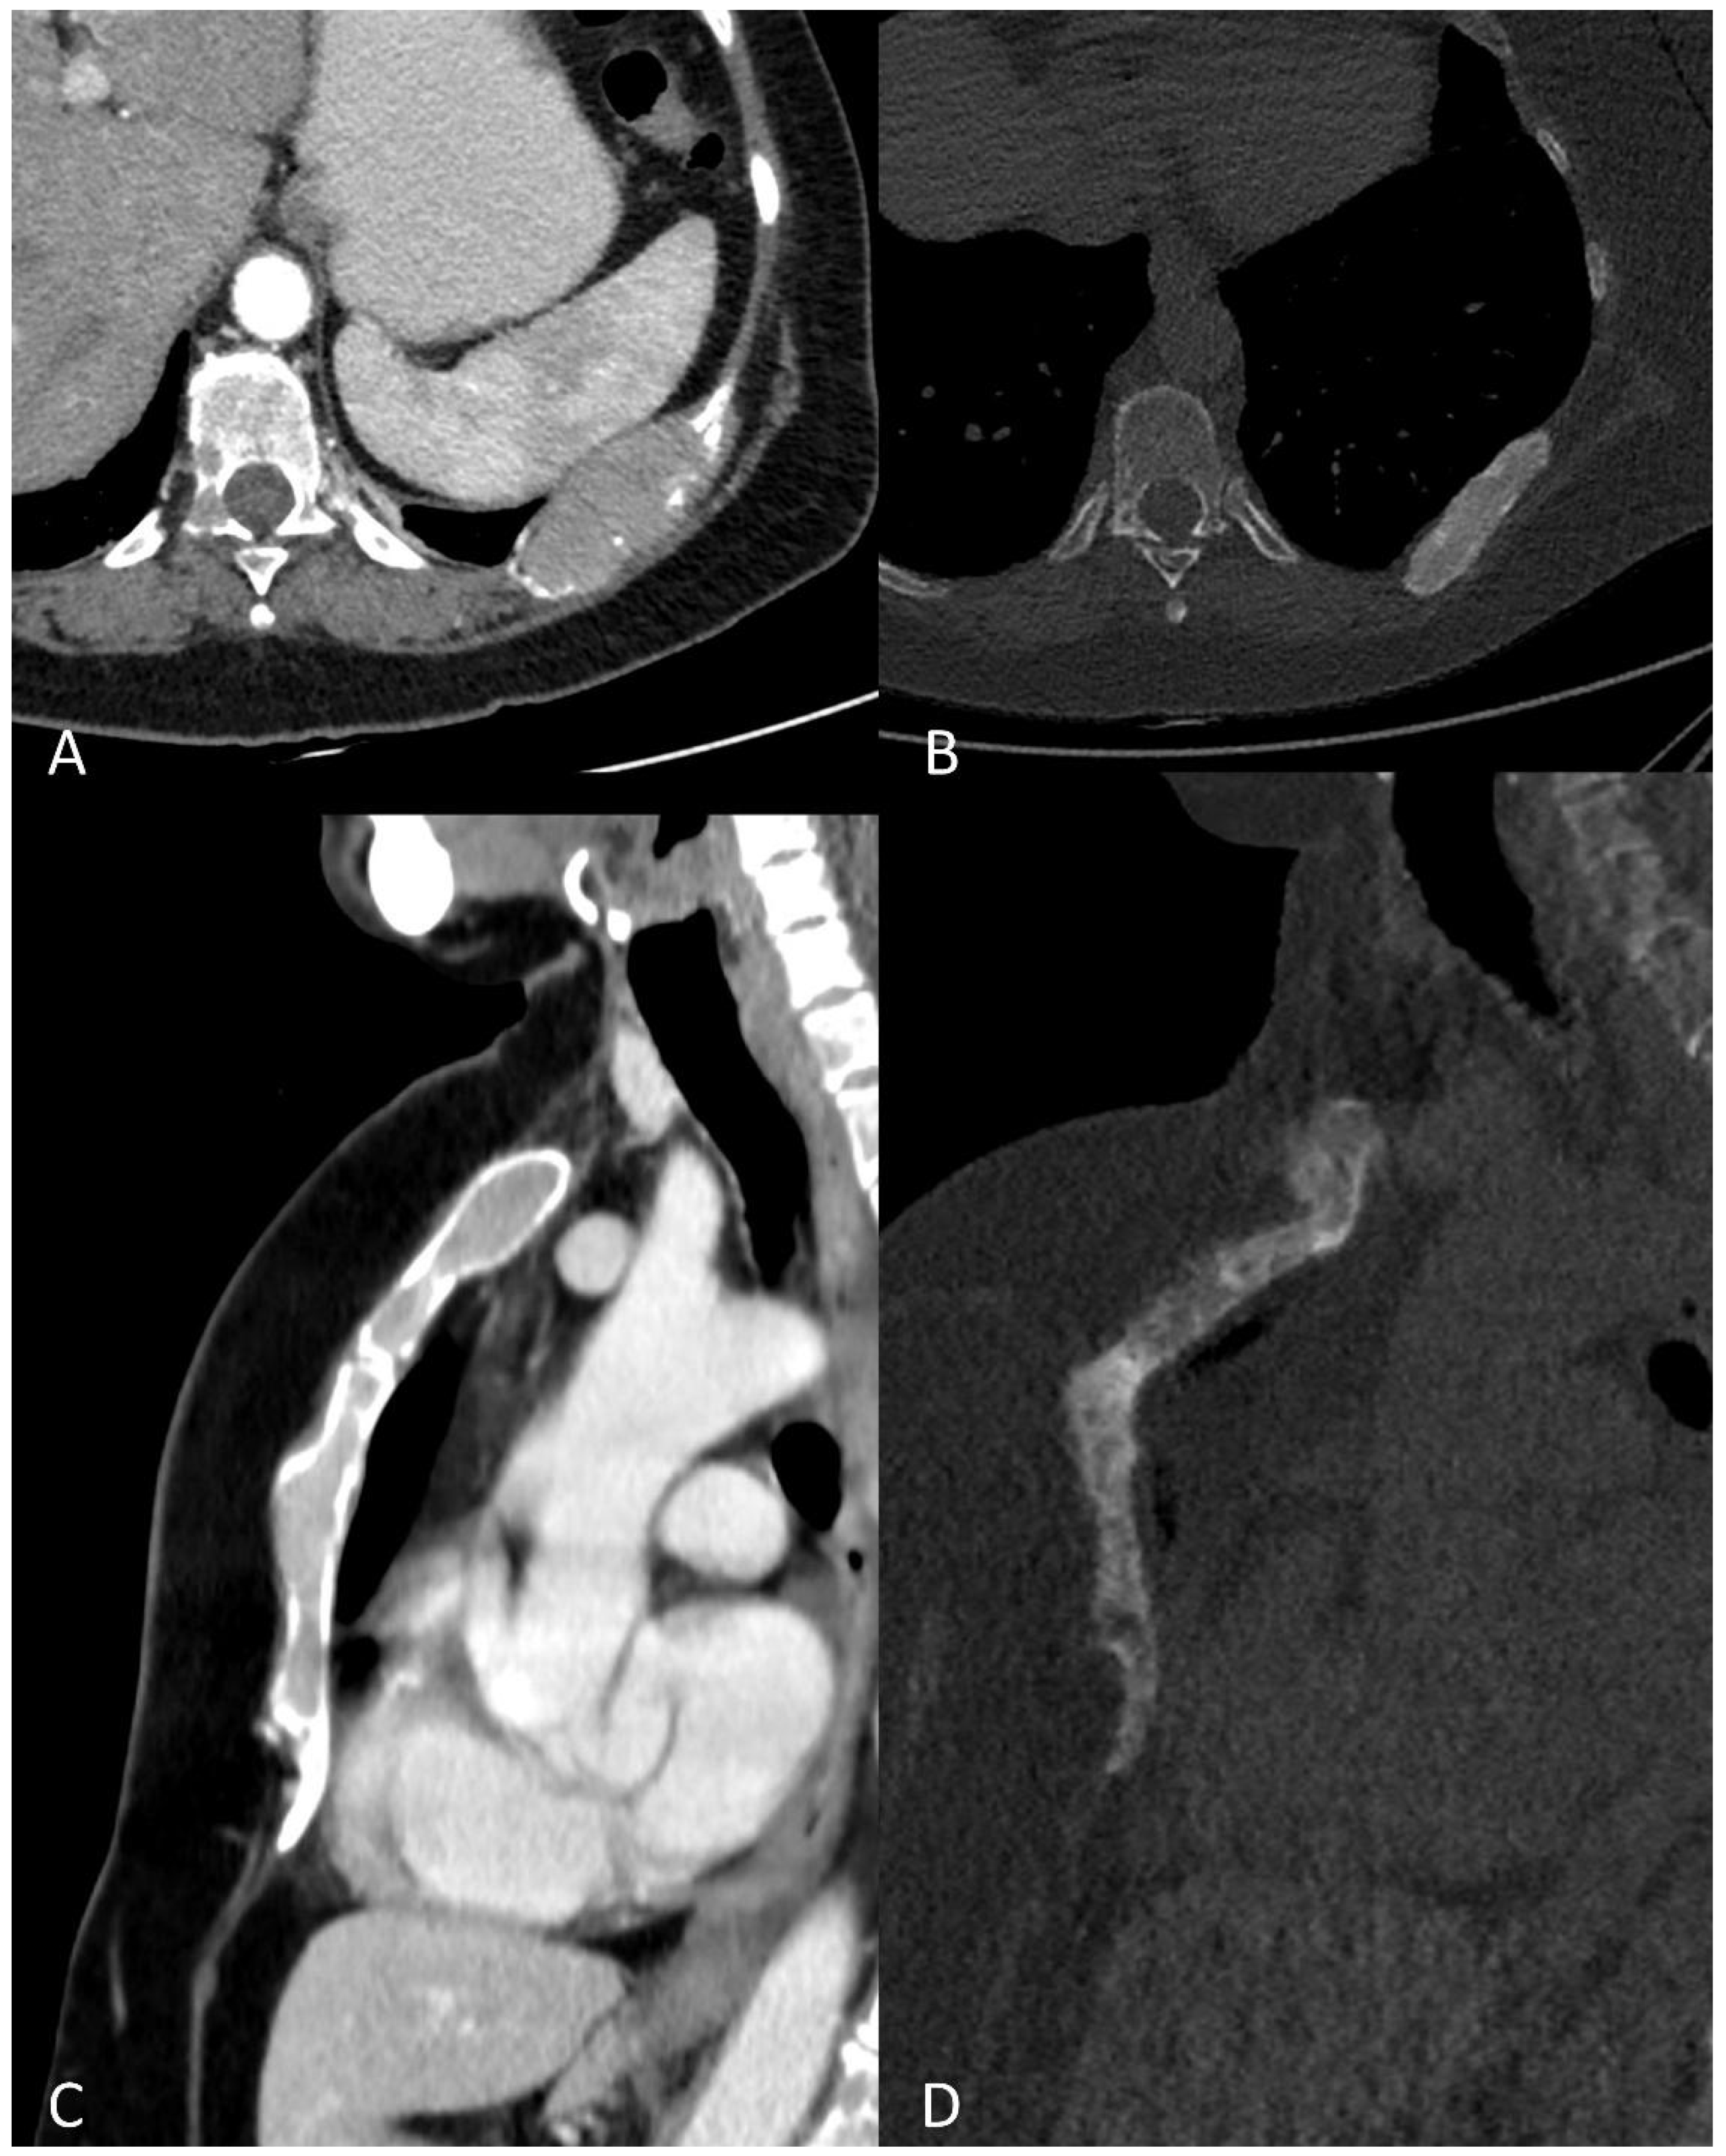

Figure 6.

Multiplanar CT images showing (A) an osteolytic lesion of a rib, with (B) development of sclerosis and size-reduction after treatment. (C) Diffuse hyperdense myeloma deposits in the medullary cavities of the sternum with (D) development of sclerosis and size-reduction after treatment.